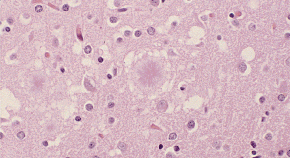

Two sets of studies, using different approaches, provide convincing evidence that the new variant of Creutzfeldt-Jakob disease (vCJD) is caused by the agent that is responsible for BSE in cattle. Like Creutzfeldt-Jakob disease itself, vCJD is a human neurological disorder that leads to brain damage and death; but it is clinically and pathologically distinct, not least in afflicting younger people. The new studies cannot however tell us anything about a crucial issue — the future number of cases of this variant disease.